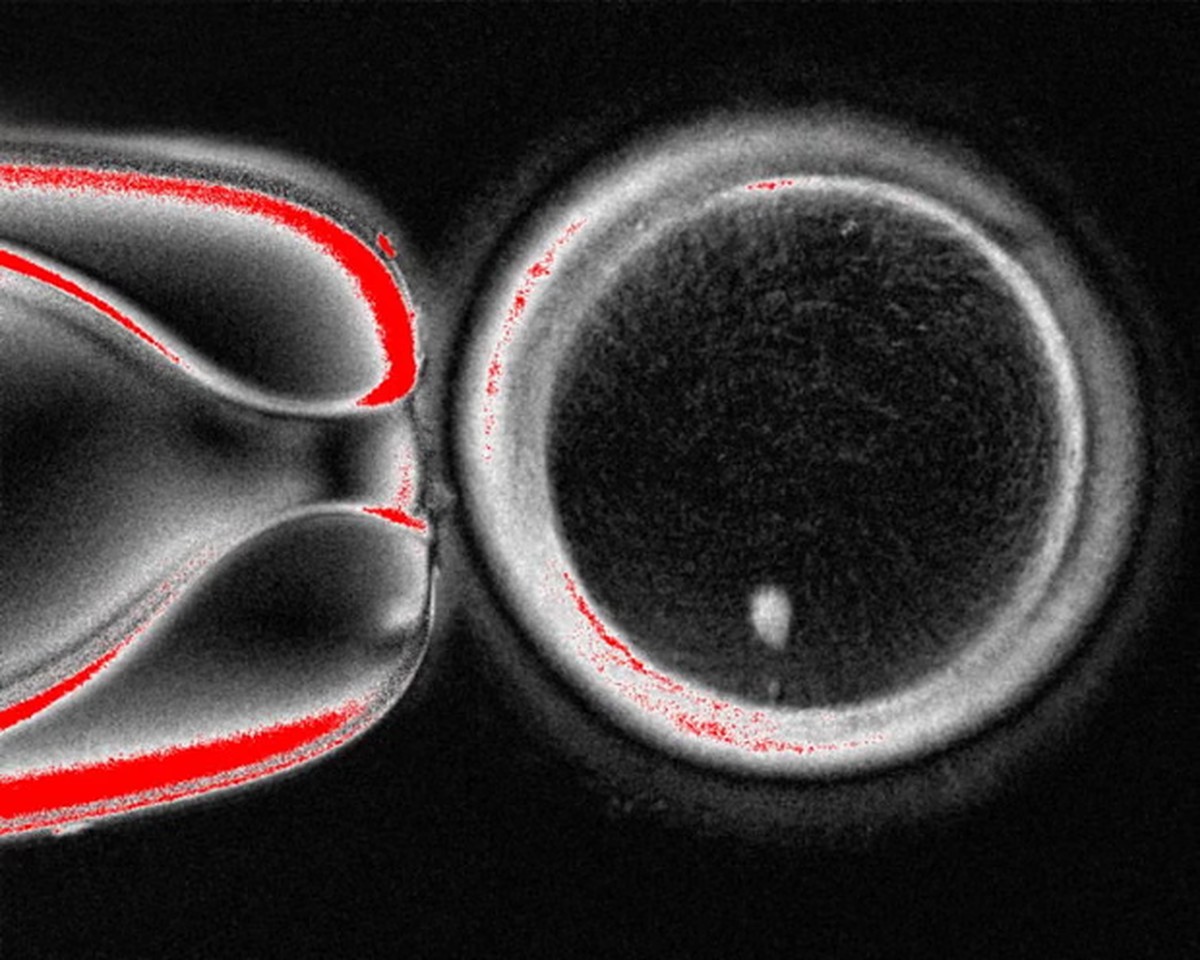

Embrião feito em laboratório consegue produzir sua...